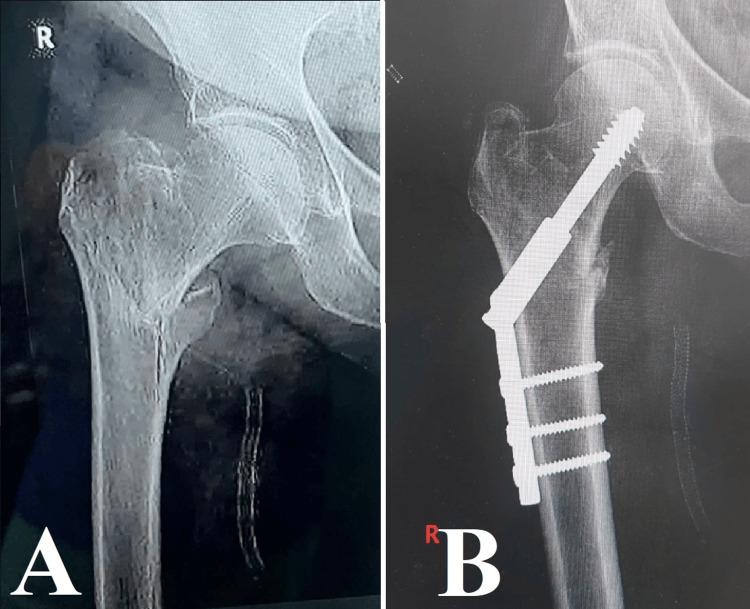

Managing osteoporotic fractures in older individuals is a difficult task in orthopedic surgery. It requires a careful approach that combines advanced diagnostic methods, customized surgical treatments, and comprehensive rehabilitation strategies. This article presents the results of an analysis carried out at the University Emergency Hospital, Bucharest. The analysis specifically examines the treatment of osteoporotic fractures using different osteosynthesis techniques. Although diagnostic tools like dual-energy X-ray absorptiometry (DXA) and Fracture Risk Assessment Tool (FRAX) have improved, a considerable number of fractures still happen in people who do not have obvious osteoporosis. This emphasizes the importance of using additional diagnostic measures such as high-resolution peripheral quantitative computed tomography (HR-pQCT) and quantitative computed tomography (QCT) to improve the accuracy of predictions. The study demonstrates the intricate nature of surgical decision-making and the significance of adjusting techniques to meet the specific needs of each patient. An instance of osteosynthesis failure resulting from the inappropriate choice of method highlighted the crucial significance of a thorough preoperative assessment. The discussion highlights the importance of early mobilization and rehabilitation in reducing the risks associated with prolonged immobilization and improving patient recovery. This paper strongly supports the use of evidence-based and patient-centered methods in the management of osteoporotic fractures. It emphasizes the importance of utilizing the most recent advancements in diagnostic and surgical technologies. Promising advancements in orthopedic medicine lie in the future, particularly in the integration of interdisciplinary research and personalized medicine. These advancements have the potential to enhance patient outcomes in this population that is at high risk.

在老年个体中处理骨质疏松性骨折是骨科手术中的一项艰巨任务。这需要一种谨慎的方法,将先进的诊断方法、定制的手术治疗和全面的康复策略结合起来。本文介绍了在布加勒斯特大学急诊医院进行的一项分析结果。该分析具体研究了使用不同骨固定技术治疗骨质疏松性骨折的情况。尽管双能X线吸收法(DXA)和骨折风险评估工具(FRAX)等诊断工具有所改进,但在没有明显骨质疏松的人群中仍有相当数量的骨折发生。这强调了使用高分辨率外周定量计算机断层扫描(HR-pQCT)和定量计算机断层扫描(QCT)等额外诊断措施以提高预测准确性的重要性。该研究证明了手术决策的复杂性以及根据每个患者的具体需求调整技术的重要性。因方法选择不当导致骨固定失败的一个实例突出了全面术前评估的关键意义。讨论强调了早期活动和康复在降低与长期固定相关的风险以及改善患者恢复方面的重要性。本文强烈支持在骨质疏松性骨折管理中使用基于证据和以患者为中心的方法。它强调了利用诊断和手术技术最新进展的重要性。骨科医学未来有充满希望的进展,特别是在跨学科研究和个性化医学的整合方面。这些进展有可能改善这一高危人群的患者预后。